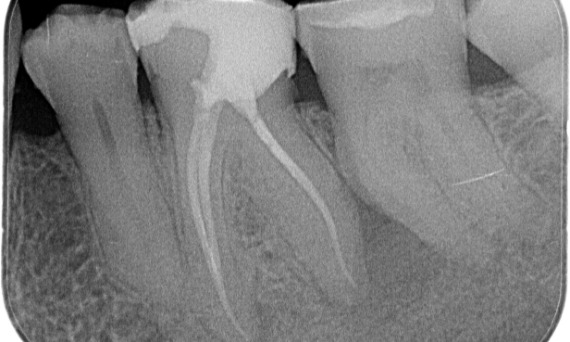

Antes: No exame, havia uma lesão de cárie dental relacionada ao primeiro molar inferior direito. O exame radiográfico revelou proximidade da lesão ao corno pulpar e, combinando-a com a queixa principal, concluiu-se um diagnóstico final de pulpite crônica irreversível.

Depois: A cavidade de acesso foi realizada da maneira mais conservadora possível. TruNatomy foi o sistema de escolha devido à idade do paciente jovem. Precisávamos preservar a dentina o máximo possível para aumentar a capacidade do dente de superar a carga oclusal e aumentar a longevidade da restauração final.

Dr. Ahmed Hussein Abuelezz (PhD em Endodontia)

Cairo, Egito